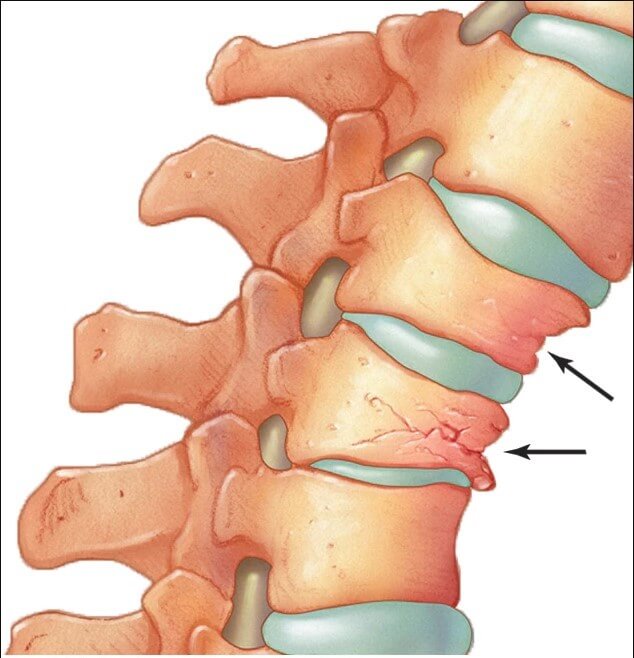

Άμεση συνέπεια ενός οστεοπορωτικού κατάγματος της σπονδυλικής στήλης είναι ότι ο ασθενής νιώθει έντονο πόνο στην πλάτη ή τη μέση, ο οποίος επιτείνεται κατά την ορθοστασία και υποχωρεί όταν ξαπλώνει, ενώ κάποιες φορές μπορεί να εντοπίζεται σε άλλο σημείο από αυτό του κατάγματος ή να αντανακλά στο θώρακα, την κοιλιά ή στο πόδι. Επακόλουθο ενός οστεοπορωτικού κατάγματος είναι η σφηνοειδής παραμόρφωση και η απώλεια ύψους του σπονδύλου με αποτέλεσμα την κύφωση, τον περιορισμό της κινητικότητας της σπονδυλικής στήλης και τον χρόνιο πόνο. Τυχόν δε πίεση νευρικών στοιχείων από σπασμένα κομμάτια του σπονδύλου μπορεί να προκαλέσουν σοβαρές νευρολογικές επιπλοκές.